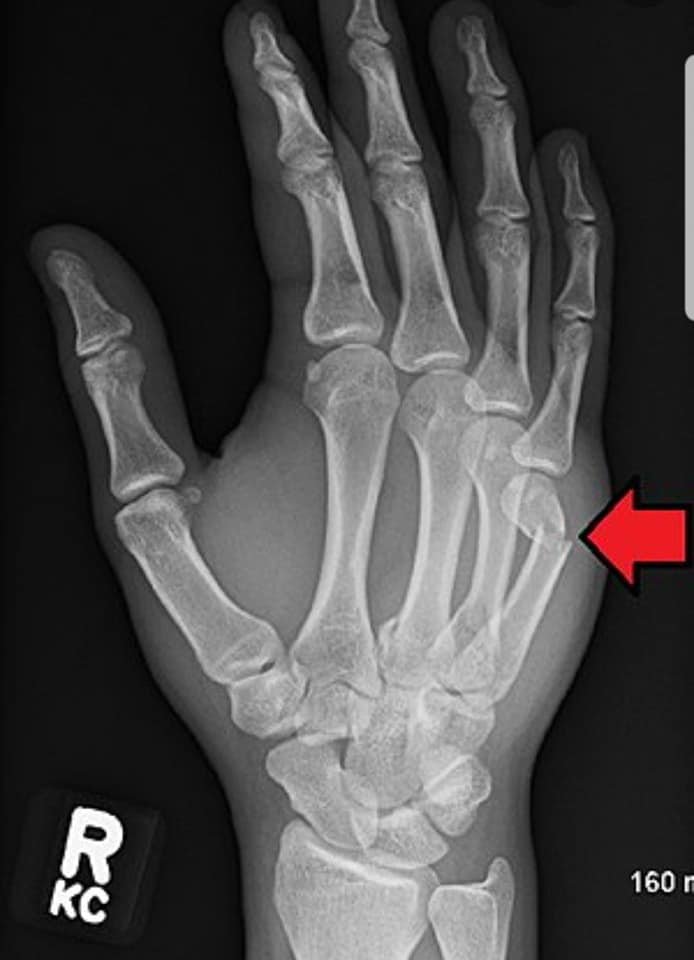

"Сээрний ясыг гараараа цохих нь шууд утгаараа, ясыг ясаар цохиж байгаа хэрэг. Мэдээж аль нэг яс нь хугарна. Сээрний яс хугарах нь хэнд ч хамаагүй, үр өгөөжгүй. Харин тухайн хүний өөрийнх нь яс хугарвал хохиролтой. Мөн зөөлөн эд гэмтсэнээр хаван, хавдар үүсэж нян бактери бий болно. Үүнээс болж гараа тайруулах ч эрсдэлтэй. Ямар нэг гадны шалтгаангүй, зүгээр байж байгаад энэ мэт өөрийгөө гэмтээж хохирох, эмч нарын ачааллыг нэмэх нь асуудал дагуулж байна.

Сээрний яс хугарах нь хэнд ч хамаагүй, үр өгөөжгүй. Харин тухайн хүний өөрийнх нь яс хугарвал хохиролтой. Мөн зөөлөн эд гэмтсэнээр хаван, хавдар үүсэж, нян бактери бий болно. Үүнээс болж гараа тайруулах ч эрсдэлтэй.